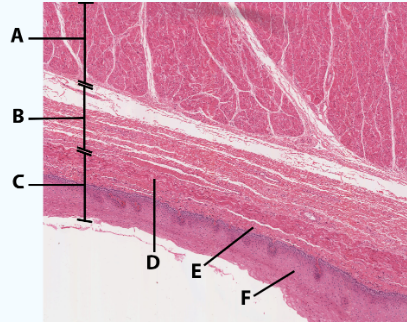

A

Muscularis

B

Submucosa

C

Mucosa

D

Muscularis mucosa

E

lamina propria

F

stratified squamous epithelial tissue

area

Esophagus